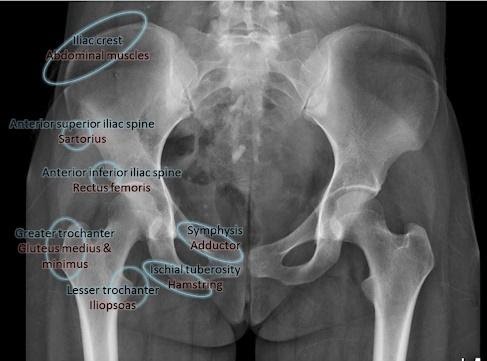

The pelvic apophyses appear, then fuse, at variable ages. Notably the ischial (hamstring origin) and anterior superior iliac spine (Tensor Fascia Lata and Sartorius) sometimes ossify well into late teens and early 20s. Pubic apophyses can be as delayed as late 20’s! See Table 1 below and bear this in mind even if you think you are treating an adult.

Apophysitis (overload of the immature growth plate leading to micro-stress and inflammation) can affect numerous pelvic sites (figure 5 [1]).